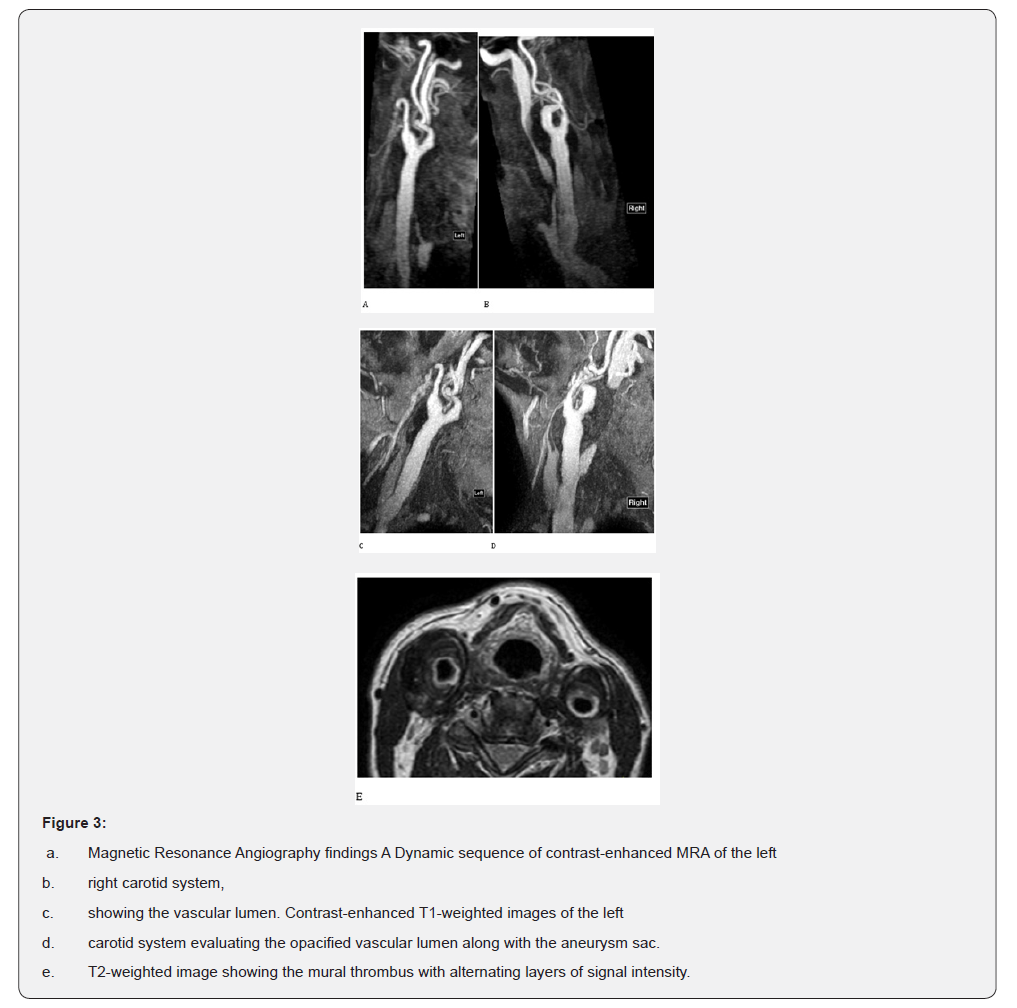

Following the intravenous administration of 2.4 ml of SonoVue, Contrast-Enhanced Ultrasound (CEUS) improved visualization of blood flow and detailed delineation of vascular lumen, confidently excluding the presence of slow flow within a hidden false lumen. The suspected diagnosis of dissection was thus excluded and the diagnosis of simple aneurysms with mural thrombus was suggested (Figure1). Multi Detector Computed Tomography Angiography (MDCTA) of the carotid arteries confirmed the presence of bilateral aneurysms with significant mural thrombus affecting carotid bifurcations and excluded the presence of any abnormalities in the intracranial circulation (Figure 2). The patient also underwent contrast-enhanced Magnetic Resonance Angiography (MRA) of the carotid arteries. The carotid’s lumen was evaluated on the contrast-enhanced angiography sequence while the mural thrombus appeared with heterogeneous low signal intensity on T2-weighted images (Figure 3). Similarly, to B-mode US, the thrombus showed an alternating pattern with layers of slightly higher signal intensity and areas of lower signal intensity. This pattern was accurately demonstrated on MRI and B-mode US with adequate contrast but was less well appreciated on MDCTA, where it appeared homogeneously hypodense. Nevertheless, MDCTA could delineate with better spatial resolution the exact borders of the vascular lumen.